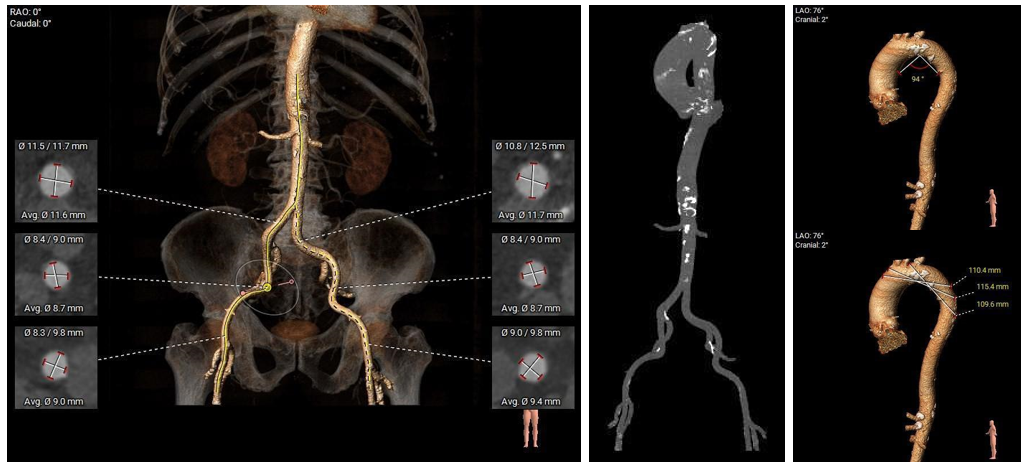

术前CT评估:

•Type 1 型二叶式主动脉瓣,R-N间钙化融合嵴,瓣叶增厚伴轻中度钙化,左窦内钙化延伸至瓣环平面;左室流出道呈敞口型。

•冠脉开口高度可,左冠瓣叶冗长,左冠切线位瓣叶长度>冠脉开口到瓣叶附着缘距离;冠脉可见散在钙化斑块。

•瓦氏窦、窦管交界内径尚可,升主动脉扩张;左室腔内径正常,心室壁厚度尚可。

•瓣环水平夹角为57°,主动脉弓弓距、角度可,升主动脉未见明显扭曲。

•双侧股髂动脉未见扭曲,主动脉弓、降主动脉、腹主动脉、右髂总动脉可见多发散在钙化斑块,股动脉穿刺处未见明显钙化,右股动脉分叉处较高,入路血管直径尚可。

外周血管入路评估